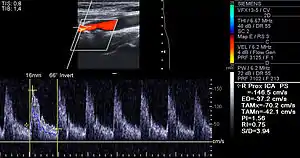

Besides the traditional diagnostic methods such as angiography and stress-testing, other detection techniques have been developed in the past decades for earlier detection of atherosclerotic disease. Some of the detection approaches include anatomical detection and physiologic measurement.

Examples of anatomical detection methods include coronary calcium scoring by CT, carotid IMT (intimal media thickness) measurement by ultrasound, and intravascular ultrasound (IVUS). Examples of physiologic measurement methods include lipoprotein subclass analysis, HbA1c, hs-CRP, and homocysteine. Both anatomic and physiologic methods allow early detection before symptoms show up, disease staging and tracking of disease progression. Anatomic methods are more expensive and some of them are invasive in nature, such as IVUS. On the other hand, physiologic methods are often less expensive and safer. But they do not quantify the current state of the disease or directly track progression. In recent years, developments in nuclear imaging techniques such as PET and SPECT have provided ways of estimating the severity of atherosclerotic plaques.